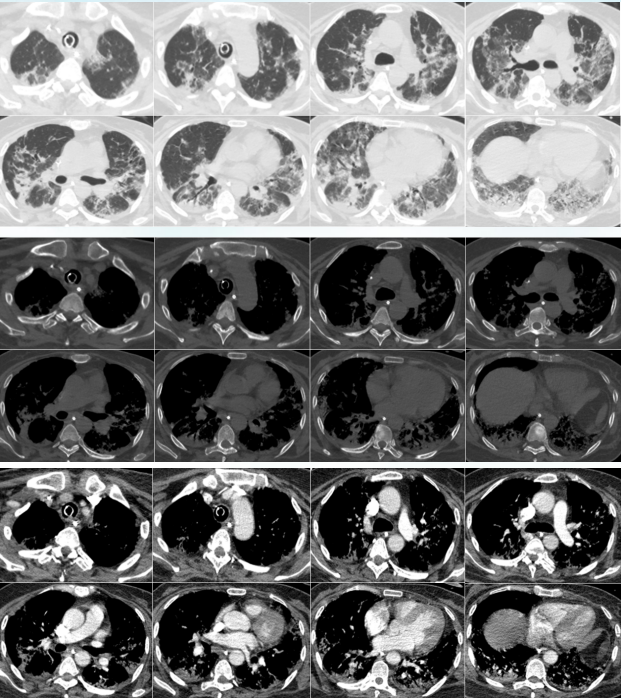

• 胸部+肺动脉CTA(2024-06-07):双肺散在炎性病变伴间质改变,部分实变不张;所示肺动脉CTA未见确切栓塞征象(图2)

图片

2  患者胸部CT(2024-06-07)

视频:患者胸部CT变化情况

注:左侧为2024年6月19日胸部CT,右侧为2024年6月7日胸部CT。